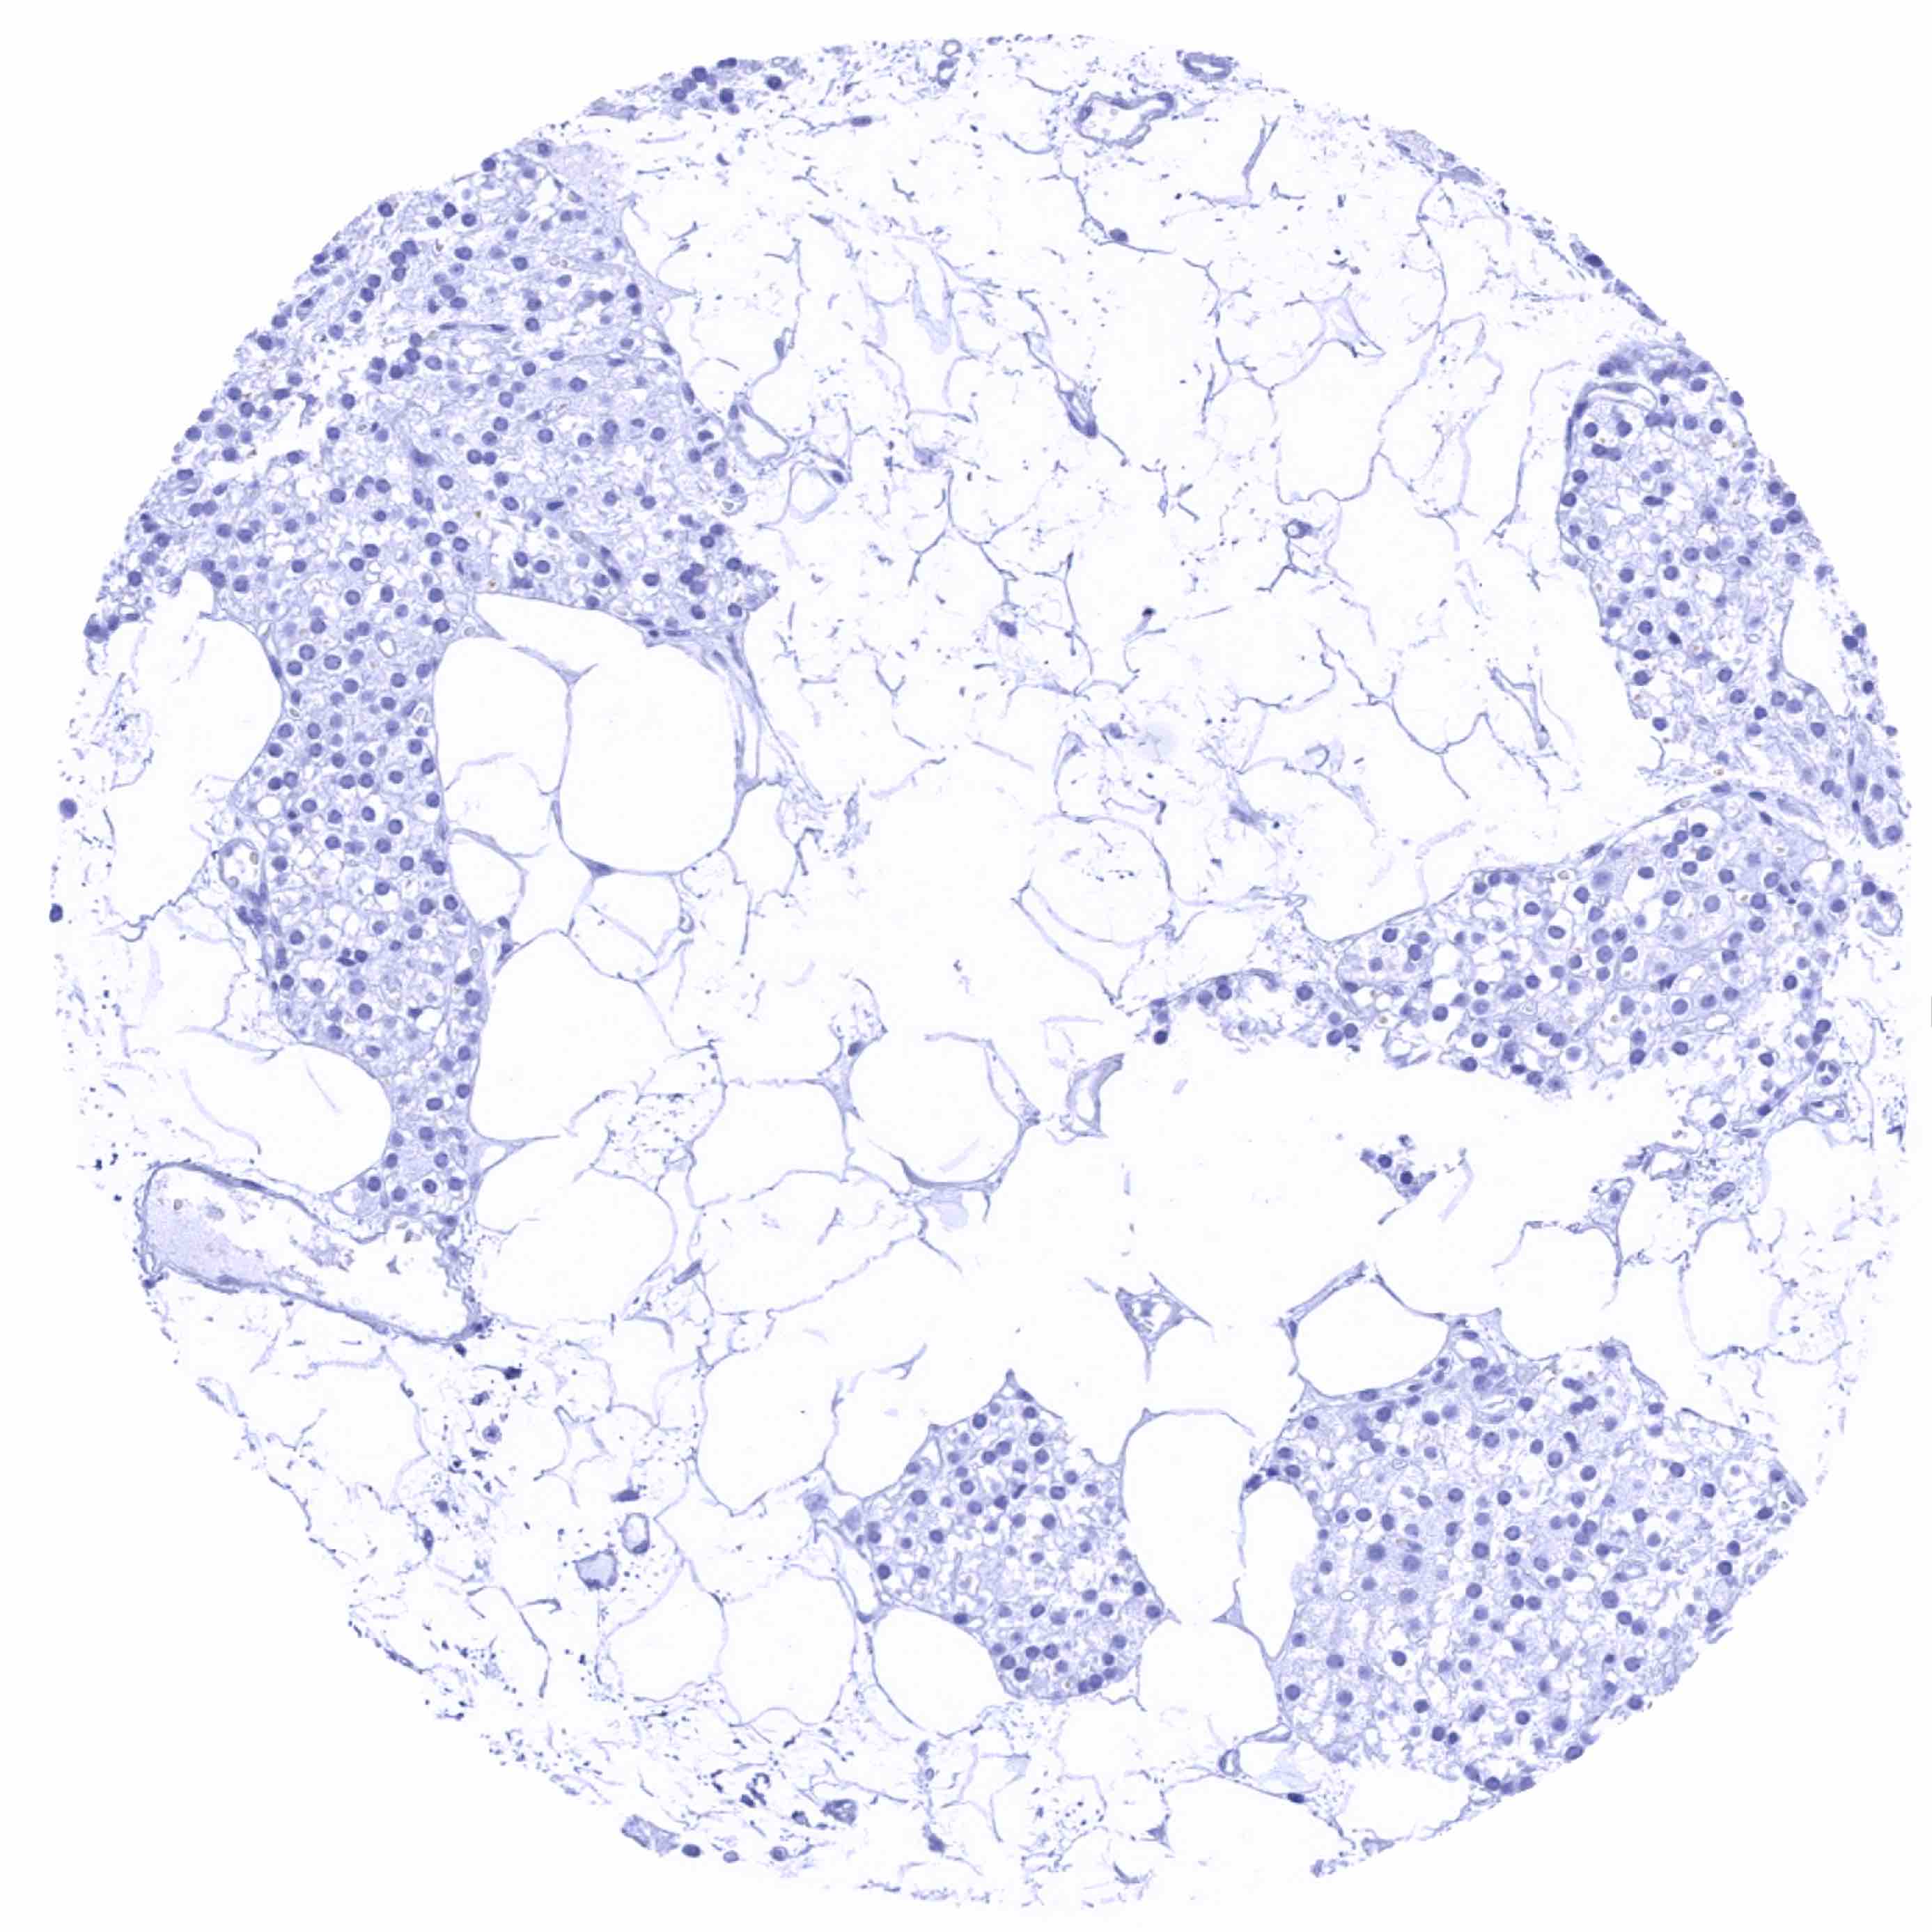

Fat